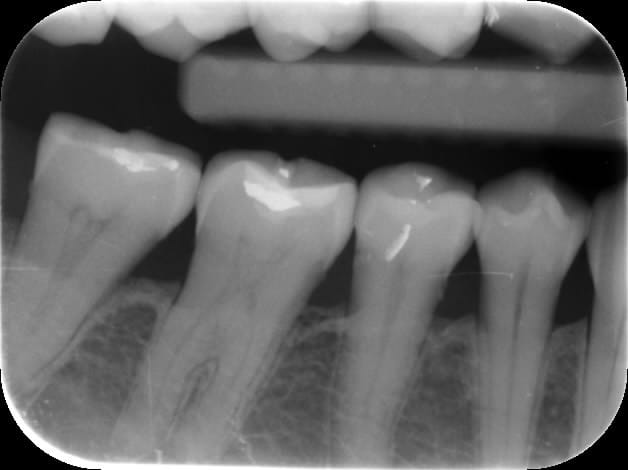

ton abces est bien entre la pm et la mol

au vu des radios les corticales sont la donc ce n'est pas un parodontite en phase evolutive c'est une paro de l'adulte surement debutante ou traitée et stable ( pas d'info sur l'histoire de la bouche de ta patiente )

une pano minmum pour s'assurer de l'etat global de la denture .......si doute bilan retroalveolaire

il semblerait d'aprés la radio,qu'il y ait une reconstitution distale de la prémolaire?,sinon à quoi correspondraient ces traits blancs,?

en plus la 6 présente une légère fissure de l'émail au niveau de la "fossette"qui pourrait provoquer un tassement alimentaire